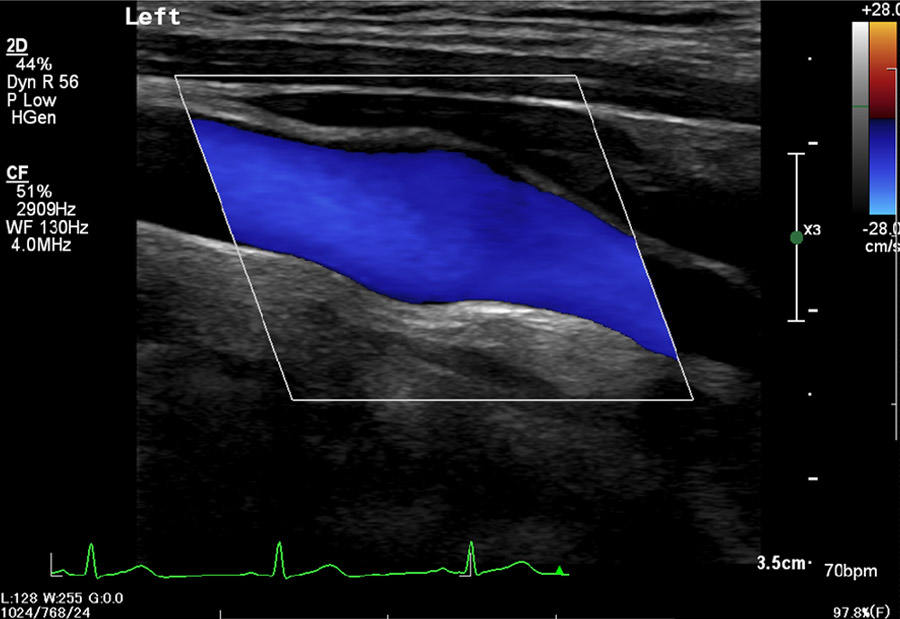

血管エコー検査

頸部血管エコーの場合、脳血管障害(脳梗塞など)のある方、血液検査で異常のある方(コレステロールや血糖値が高いなど)、高血圧症や糖尿病の方、その他の検査で動脈硬化が指摘された場合にも行います。

下肢エコーは歩行時の足の痛みやしびれの原因(閉塞性動脈硬化症の有無)、脳梗塞・足のだるさ、むくみの原因(深部静脈血栓や静脈瘤の有無)を見つけるために行います。

検査内容

超音波を首や足などにあて、頸部血管や下肢血管など身体の動脈や静脈の血管内の状態を見ることができます。

所要時間

15~40分

検査でわかること

頸部血管エコーや下肢血管エコーなど、身体の静脈や動脈の血管を色々な方向から見ることによって、血管の太さや走行、血流の状態、血管壁の状態(硬さや血栓の有無、血管内側の詰まり具合)を見つける事ができます。

注意事項

ベッドに横になっていただき、超音波ゼリーを対象部位にぬり、プローブをあてながら検査をします。ゼリーは少し冷たいです。食事制限は特にありません。